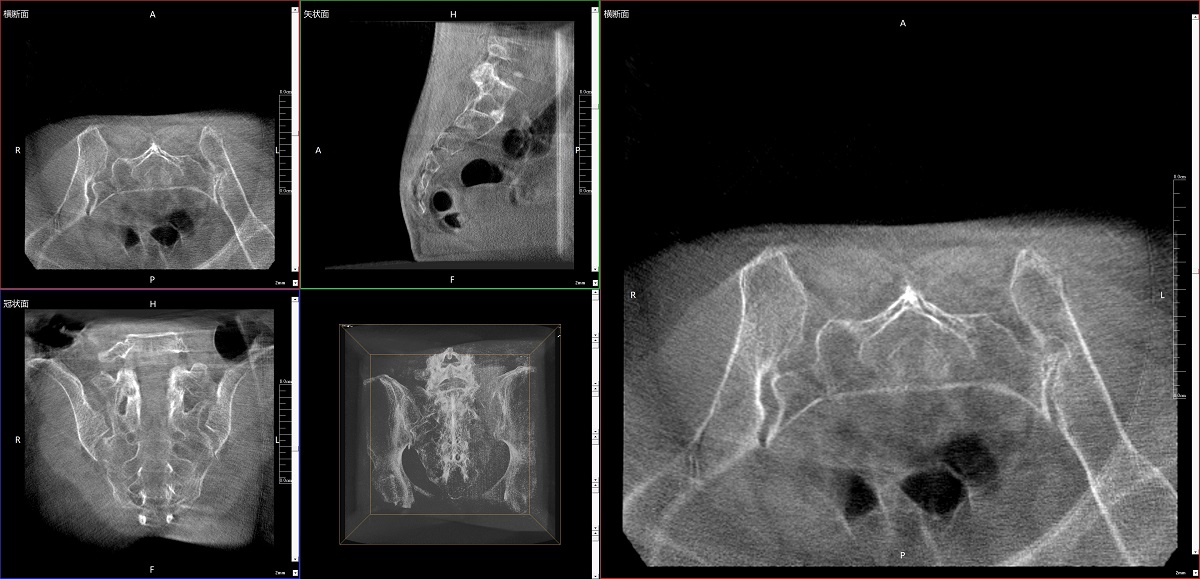

在骨科手術(shù)中,影像相當于醫生的“眼睛”,要先“看得清",才能“算得準” “打得穩”。普愛(ài)醫療第三代平板三維C形臂協(xié)同醫院創(chuàng )傷導航機器人已開(kāi)展多例“骨盆骨折微創(chuàng )手術(shù)”,成為上海市第七人民醫院手術(shù)技術(shù)創(chuàng )新的一大亮點(diǎn)。

普愛(ài)醫療第三代平板三維C形臂出色的二維透視和術(shù)中三維成像效果,為機器人提供了精確的術(shù)中影像依據,協(xié)同提升手術(shù)整體的精準度和效率,為患者帶來(lái)了更安全、更高效的醫療服務(wù)體驗。